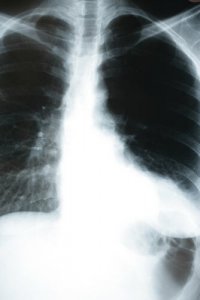

How Pneumonia Affects the Body

There are an estimated 2 to 10 cases of pneumonia per 1,000 inhabitants per year. Of those cases, between 20 and 35% require hospitalization. In patients with other illnesses, mortality is 1%, but it can increase to 40% in hospitalized patients, especially those in intensive care. Depending on a patient’s situation, pneumonia can be fatal.